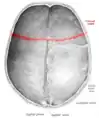

در جمجمه سر انسان، درز تاجی (انگلیسی: Coronal suture) میان استخوان پیشانی و دو استخوان آهیانه قرار دارد. درز تاجی در میان استخوانهای سر، بر پیش سر، بر آن موضعی است که کنارهٔ کلاه بر آن مینشیند. در قدیم به آن درز اکلیلی هم میگفتند.

![]() Superior view of the skull. ("Coronal suture" in red.) | |

درز تاجی با اتصال Pterion دو طرف مسیر سطحی آن مشخص میگردد.